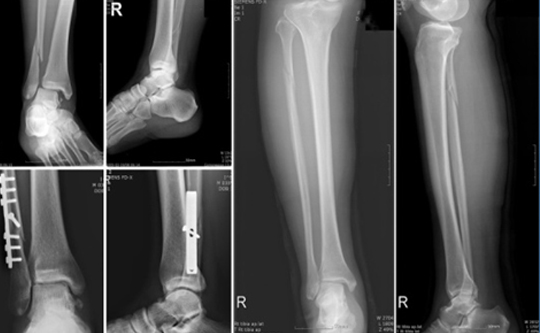

치료의 방침은 크게 도수 정복 후 고정을 통한 비수술적 방법과 관혈적 정복 및 내고정을 통한 수술적 방법으로 크게 나눌 수 있습니다.

족부 족관절 골절 이미지

비수술적 방법은 대게 전위가 없는 내과나 외과의 단독 골절에서, 또는 수술적 치료를 요하나 환자의 나이나 전신 상태가 수술을 시행하기에 어려운 경우 선택을 하게 되며, 대게 6에서 8주 동안 부목, 석고붕대 등의 고정을 통하여 골절의 유합을 되게 합니다.

그러나, 대부분의 양과 골절이나 삼과 골절은 전위되어 있으며, 이를 마취없이 도수 정복하기는 어렵고, 수술적 가료를 시행하게 됩니다. 골절 후 시간이 지날수록 부종이 심해지고 골다공증이 진행되므로 환자의 상태가 허락한다면, 가능한 수술을 빨리 시행하는 것이 좋습니다. 단, 혈성 수포나 심한 부종이 있는 경우 수술을 연기하는 것이 바람직합니다. 예정된 수술창 부위에 발생한 수포의 경우 터지지 않기까지는 감염성이 없으며, 이에 대한 처치로 저절로 소실될 때까지 기다리거나, 심한 경우 괴사 조직 제거술 후에 치유되고 나서 수술을 시행합니다.